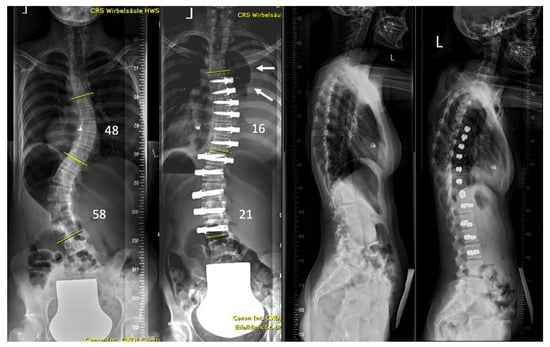

| Patient | Age (Years) | Sex | Curve Type | Instrumented Levels | Complication | Time to Diagnosis | Side of the Complication | Symptoms | Treatment |

|---|---|---|---|---|---|---|---|---|---|

| 1 | 13.3 | F | 2 | T5-T12 right T12-L4 left | Pleural effusion | 2 weeks | Right | Minor dyspnea | Ultrasound, conservative treatment |

| 2 | 17.6 | F | 4 | T6-L1 right | Pleural effusion | 2 weeks | Right | Dyspnea, fatigue | 2 × aspiration |

| 3 | 16.2 | F | 4 | T5-T12 right | Contralateral atelectasis | 2 days | Left | Severe dyspnea | Re-intubation for 3 days, 3 bronchoscopies and removal of a mucus plug |

| 4 | 17.6 | M | 1 | T9-L3 right | Pleural effusion | 4 weeks | Right | Chest pressure | Chest tube reinsertion |

| 5 | 16.2 | F | 2 | T5-T11 right T11-L3 left | Pleural effusion | 3 weeks | Bilateral | Chest pain and elevated CRP levels | Bilateral aspiration, forced diuresis and i.v. albumin treatment |

| 6 | 17.7 | F | 2 | T5-T11 right T11-L3 left | Chylothorax | 3 days | Right | None effusion, diagnosed on routine post-op X-ray | Chest tube reinsertion and dietary restriction |

| 7 | 16.8 | M | 2 | T5-T11 right T11-L4 left | Pleural effusion | 3 weeks | Left | Unknown | Explorative thoracoscopy |

| 8 | 17.9 | F | 1 | T10-L3 left | Pleural effusion | 4 days | Left | None, effusion diagnosed on routine post-op X-ray | Aspiration followed by chest tube reinsertion for recurrent effusion |

| 9 | 14.6 | F | 2 | T5-T11 right T11-L4 left | Pleural effusion | 3 weeks | Right | Fatigue, dyspnea | Chest tube reinsertion, antibiotics for co-existing pyelonephritis |

| 10 | 14.3 | F | 1 | T11-L4 left | Pleural effusion with concomitant infection | 3 weeks | Left | Sudden sharp pain in the left chest and dyspnea | Attempted aspiration and chest tube without output. VATS and six weeks antibiotitcs because of postivie culture for staph epidermidis |

| 11 | 12 | F | 4 | T5-T11 right | Haematothorax | 1 day | Right | No symptoms, significant blood loss noticed after declamping the chest tube and drop of haemoglobin levels | Emergency explorative thoracotomy using the same surgical approach. No active bleeding found but clotted hematoma |

| 12 | 13 | F | 2 | T6-T12 right T12-L4 left | Haematothorax | 6 weeks | Right | Acute chest pain | Emergency explorative thoracotomy |

| 13 | 16.5 | M | 1 | T10-L4 left | Pleural empyema | 5 weeks | Left | Dyspnea, elevated CRP levels | VATS and antibiotic therapy |

| 14 | 16.3 | F | 2 | T5-T11 right T11-L4 left | Pleural effusion | 5 weeks | Right | Dyspnea | Aspiration |